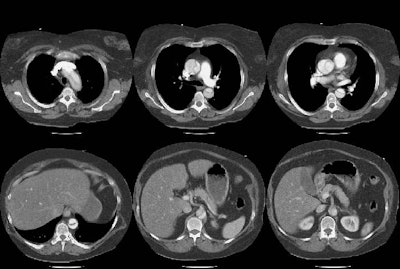

Aortic Dissection: Type A (DeBakey Type I):

The intimal flap can be clearly identified within both the ascending and descending aorta. Note that the celiac trunk and superior mesenteric artery both arise from the false lumen.